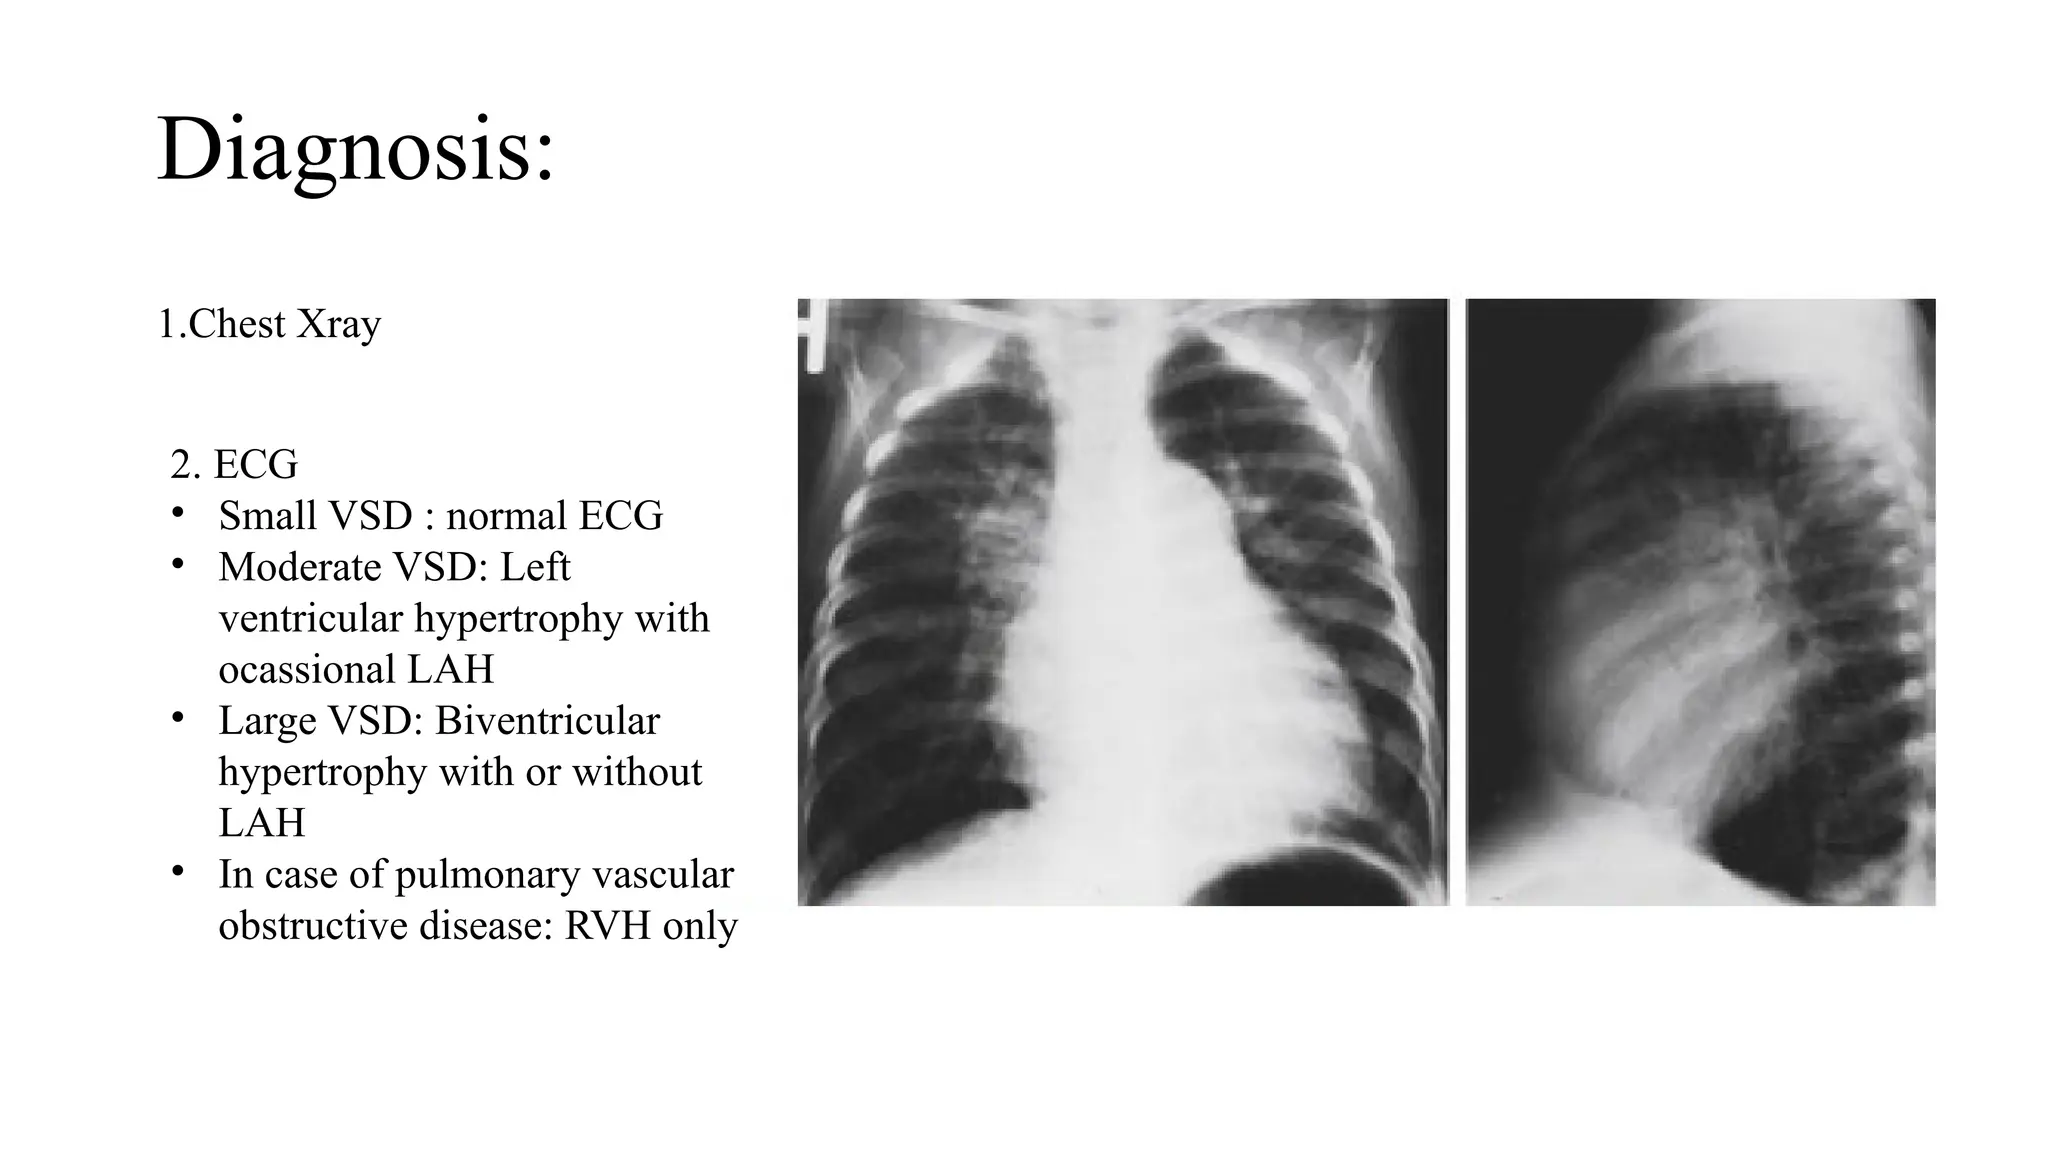

Diagnosis:

1.Chest Xray

2. ECG

• Small VSD : normal ECG

• Moderate VSD: Left

ventricular hypertrophy with

ocassional LAH

• Large VSD: Biventricular

hypertrophy with or without

LAH

• In case of pulmonary vascular

obstructive disease: RVH only